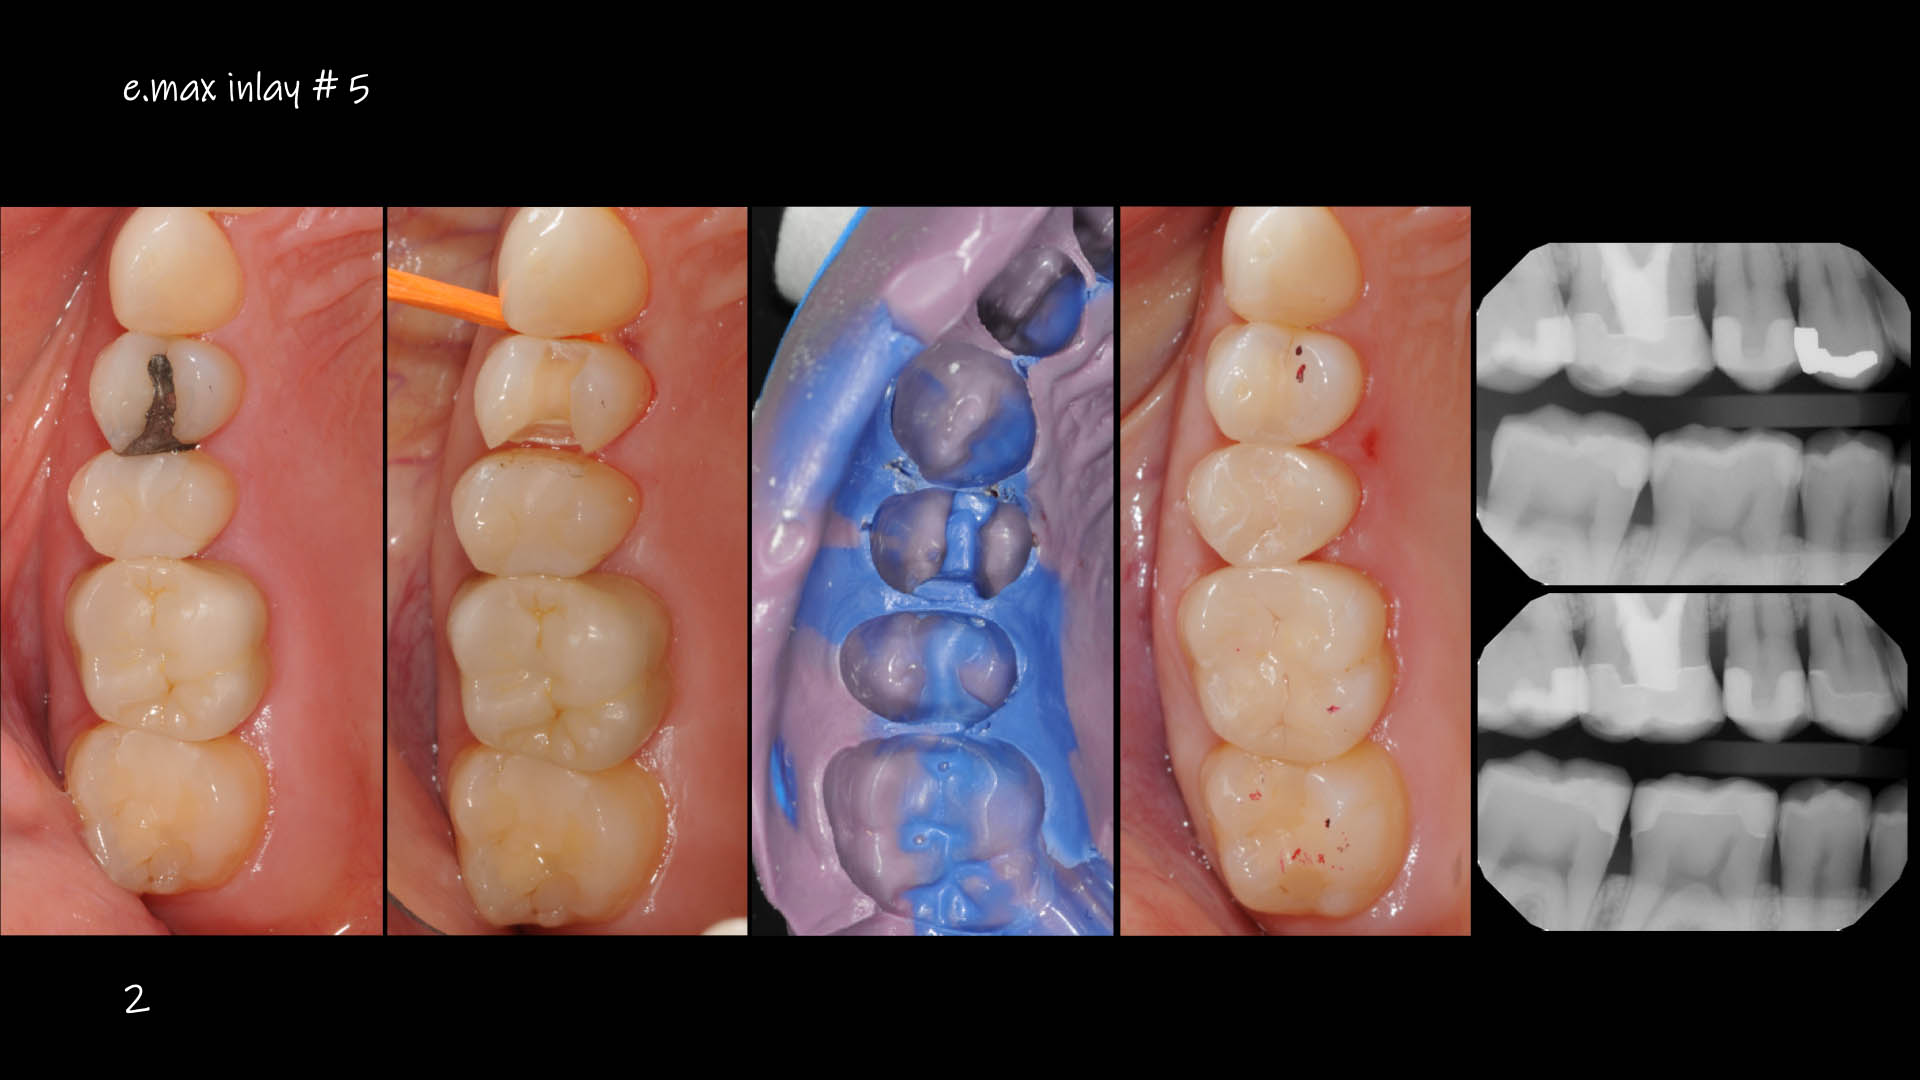

Take a glimpse into the magic of Coral Gables Dentistry through our before and after pictures. See firsthand the incredible smile makeover transformations that have brought confidence and joy to our patients.